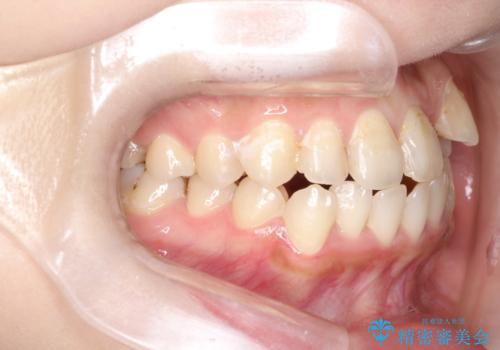

八重歯をインビザラインで非抜歯矯正

- 八重歯を主訴に来院されました。

インビザラインにて奥歯を後方に移動して八重歯が入るスペースを確保してく矯正する計画としました。

八重歯と前歯のガタガタがなくなり、歯並びがきれいになったのと、かみ合わせも改善することができました。